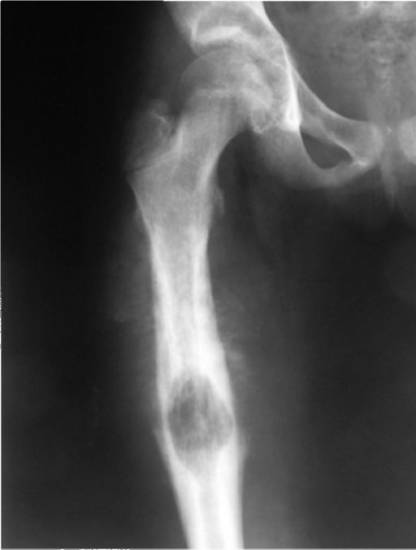

Травмы

Пациент испытывает дискомфорт и болезненные ощущения в области бедра при растяжении, переломах или травмах мягких тканей. Наиболее подвержены переломам бедра пожилые люди, которые сталкиваются с трудностями в восстановлении, так как их кости срастаются медленно и плохо.